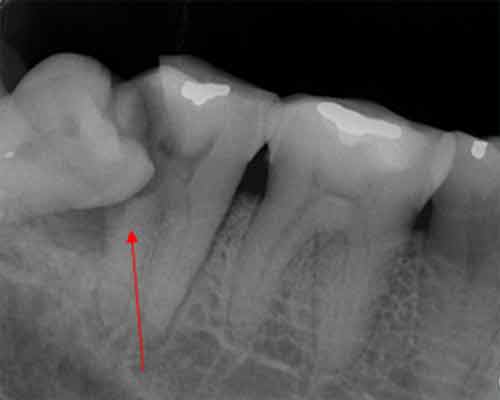

智齒造成囊腫

2011年6月拍攝